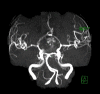

BACKGROUND Pituitary macroadenoma is a common benign tumor that usually presents with visual field defects or hormonal abnormalities. Cerebral infarction can be a complication of a large pituitary adenoma. We report a rare case of bilateral anterior cerebral arteries infarcts by a large pituitary macroadenoma with apoplexy. CASE REPORT A 48-year-old male patient presented with altered conscious level and sudden loss of vision for one-day duration. Magnetic resonance imaging of the brain showed a large seller and suprasellar hemorrhagic mass of pituitary origin, with associated bilateral areas of diffusion restriction in the frontal parasagittal regions, consistent with infarctions. Magnetic resonance angiography showed elevation and compression of A1 segment of both anterior cerebral arteries by the hemorrhagic pituitary macroadenoma. The patient underwent trans-sphenoidal resection of the pituitary adenoma, but unfortunately, ischemia was irreversible. Computed tomography (CT) done post-operatively showed hypodensity in the frontal and parietal parasagittal areas, which was also persistent in the follow up CT scans. The patient's neurological function remained poor, with GCS of 8/15, in vegetative state. CONCLUSIONS Vascular complications of the pituitary apoplexy, although uncommon, can be very severe and life threatening. Early detection of vascular compromise caused by hemorrhagic pituitary macroadenoma can prevent delay in intervention. Clinicians should also consider pituitary adenoma as a possible cause of stroke.